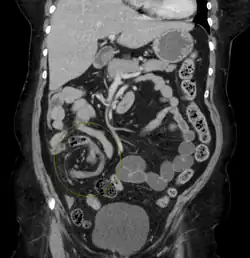

CT scan of a small bowel volvulus. It shows two juxtaposed segments of narrowing, which is the spot of mesentery rotation. The other signs indicate strangulation. -

CT scan of a cecal volvulus